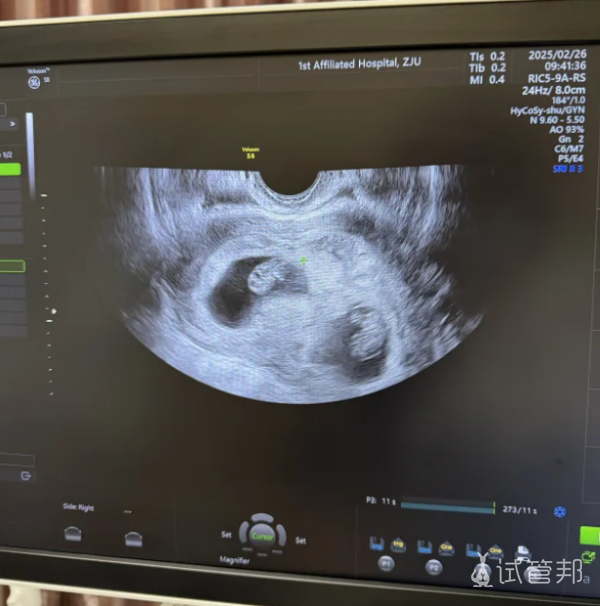

到了第40天,到医院一检查,两个胚胎都顺利着床了!那一刻,我真是又惊又喜,眼泪差点儿没掉下来。功夫不负有心人,总算是没白忙活。

上周又去医院复查了,已经孕10周了,各项指标都正常,俩宝宝都长得挺好。医生说,我这算是毕业了,接下来就等着享福了。回想起试管那段日子,确实难熬,但现在看来,一切都值了。接下来啊,我就得吃好喝好睡好,保持好心情,让俩宝贝在我肚子里健健康康地长大。